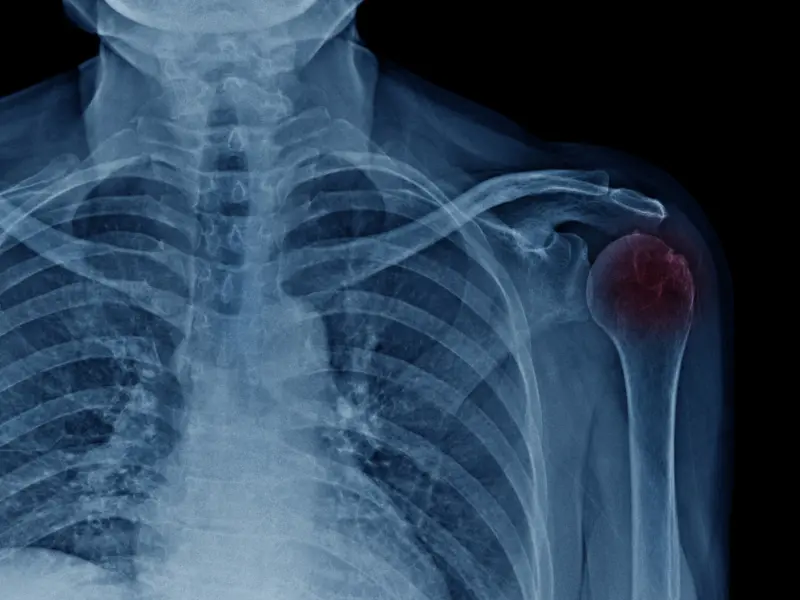

La osteoartritis acromioclavicular es una condición que afecta a la articulación acromioclavicular, situada en la parte superior del hombro, donde la clavícula se une con el acromion (una extensión del omóplato). Esta forma de osteoartritis es común, especialmente en personas mayores o en aquellos que realizan actividades repetitivas que implican el uso del hombro. En el Centro Médico Los Tilos, ubicado en Málaga, contamos con especialistas en reumatología para diagnosticar y tratar esta patología de forma eficaz.

En el Centro Médico Los Tilos, los especialistas en reumatología realizan una evaluación clínica detallada y pueden solicitar pruebas como radiografías para confirmar el diagnóstico y evaluar el grado de desgaste articular.